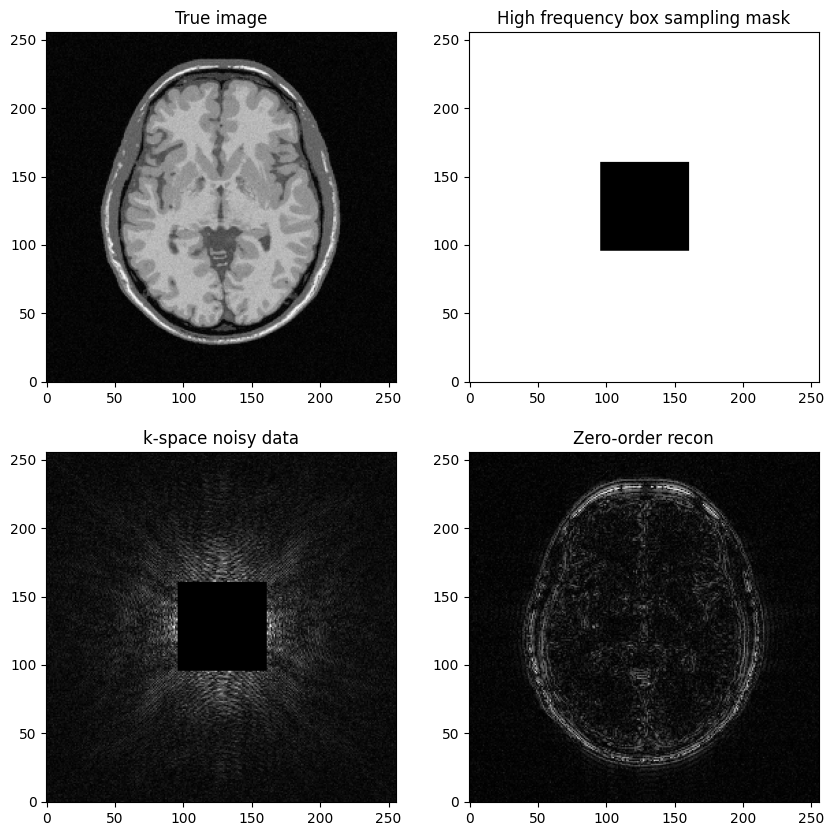

Question: Based on the previous example, try to construct a k-space mask that consists of the removing the central box centered in \((𝑘_𝑥,𝑘_𝑦)=(0,0)\).

Then, replicate the same steps:

Generate noisy masked data

Perform zero-filled MR image recon

Visualize results and study the impact of both the noise level and the mask size

axs[0,0].imshow(mri_img, cmap='Greys_r')

axs[0,0].set_title("True image")

axs[0,1].imshow(kspace_maskbox, cmap='Greys_r')

axs[0,1].set_title("High frequency box sampling mask")

axs[1,0].imshow(np.abs(kspace_data), cmap='gray', vmax=1*np.abs(kspace_data).max())

axs[1,0].set_title("k-space noisy data")

axs[1,1].imshow(np.abs(image_rec0), cmap='Greys_r')

axs[1,1].set_title("Zero-order recon")